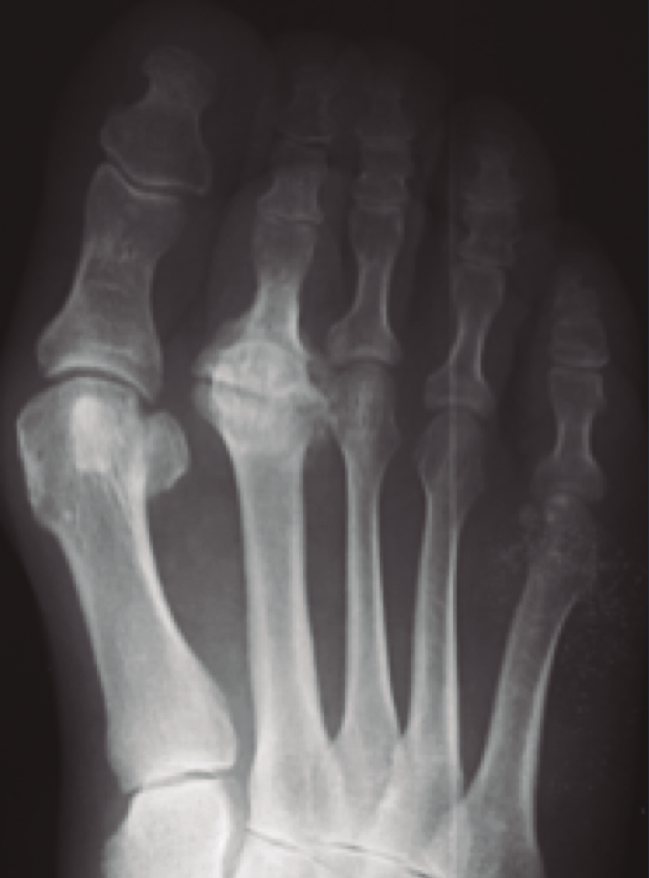

Las necrosis asépticas aparecen en aquellos puntos de nuestro aparato locomotor sometidos a importantes solicitaciones mecánicas, sea por microtraumatismos o por sobrecarga estructural. En el caso de la enfermedad de Freiberg, diversos autores(2,10,11,12) apoyan esta teoría que nosotros compartimos, ya que hemos visto muchos casos de afectación del segundo metatarsiano acompañando una insuficiencia del primer radio, sea por un hallux valgus o por un primer metatarsiano corto (Figura 2). En nuestro estudio a largo plazo sobre la enfermedad de Freiberg(13), sobre 16 pies operados, 12 padecían la sobrecarga mecánica.

Figura 2. Etiología mecánica. La enfermedad de Freiberg se asocia frecuentemente a una insuficiencia del primer radio.